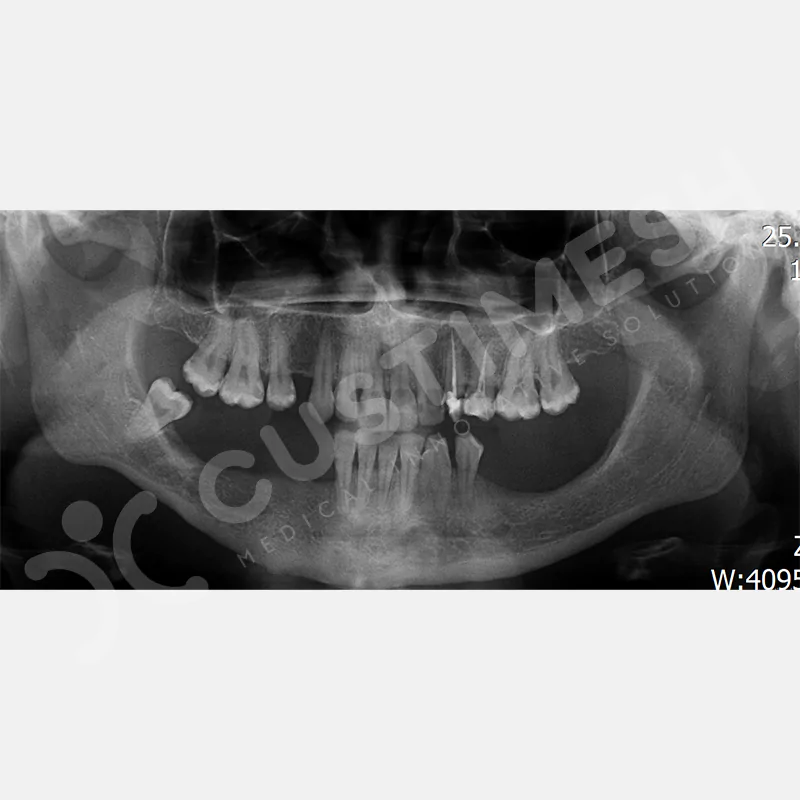

Kişiye Özel Subperiosteal İmplant, çene gelişimini tamamlamamış ve yeterli kemik desteğine sahip olmayan kişilere uygulanan, CAD/CAM teknolojisiyle kişiye özel tasarlanan bir implanttır. Bilgisayarlı tomografi görüntülerinden elde edilen verilerle, bilgisayar destekli tasarım yazılımı kullanılarak geliştirilen bu implant, lazer sinterleme yöntemi ile üretilmektedir

Modern diş hekimliğinde, çene gelişimini tamamlamamış veya ciddi kemik kaybı yaşayan hastalar için kişiye özel titanyum implantlar ile çözüm bulunmaktadır. CAD/CAM teknolojisi ve lazer sinterleme yöntemiyle üretilen bu implantlar, hastanın bireysel anatomik yapısına tam uyum sağlayarak geleneksel implantların uygulanamadığı vakalarda mükemmel bir alternatif oluşturmaktadır. Özellikle ileri derecede kemik kaybı olan hastalar için geliştirilen subperiosteal implantlar, periostun altına yerleştirilerek minimal invaziv bir yaklaşım sunarken, bilgisayarlı tomografi verileri ve sonlu eleman analizleriyle optimize edilmiş tasarımları sayesinde hem estetik hem de fonksiyonel sonuçlar garanti etmektedir. Bu yenilikçi teknoloji, tek seansta implant ve protez uygulamasına imkan vererek hastaların aynı gün doğal gülüşlerine kavuşmalarını sağlarken, kemik greftleme gibi ek işlem ihtiyacını ortadan kaldırarak cerrahi süreci büyük ölçüde kolaylaştırmaktadır. Kişiye özel tasarımı ve üstün biyouyumluluğu sayesinde, daha önce tedavisi mümkün görülmeyen kompleks vakalarda bile başarılı sonuçlar sunan bu implantlar, modern diş hekimliğinde yeni bir çağ açarak hastaların yaşam kalitesini artırmayı hedeflemektedir.

Hastanın DICOM dosyası WeTransfer aracılığıyla custimesh.case@gmail.com adresine gönderilmelidir. *AÇIKLAMA kısmına hekim adı ve Custiplate yapılacak ilgili bölge belirtilmelidir. Custiplate için, Fov genişliği tedavinin uygulanacağı bölgeyi kapsayacak şekilde 0.5 mm kesit kalınlığında Medikal CT çekilmelidir. - HEKİM ONAYI

VAKA 1

VAKA 2

VAKA 3

VAKA 4